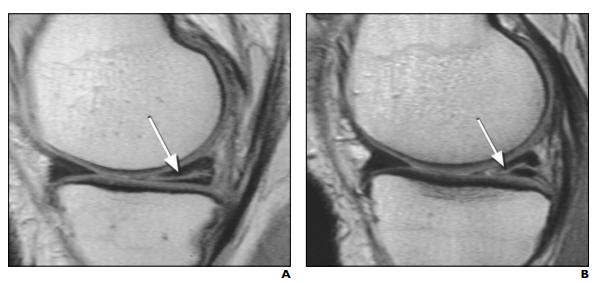

结果发现,100个人里有57个的磁共振,的确发现疼的那条腿的半月板有撕裂。而更有意思的是:

这57个人里面,有36个人的磁共振居然发现,他们的另外一条完全正常没有一点点不舒服的膝盖,居然片子上也有半月板撕裂。 36/57,这个比例高于50%啊。。。

A:患侧腿半月板异常;B(同一人)健侧腿半月板异常